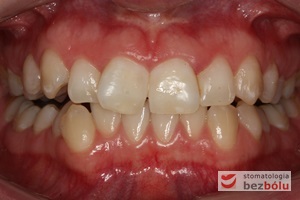

Pacjentka lat 22 zgłosiła się do naszej placówki celem podjęcia leczenia ortodontycznego. Głównym oczekiwaniem pacjentki była poprawa estetyki uśmiechu oraz brak ekstrakcji zębów na drodze do jej uzyskania. Ze względu na liczne stłoczenia zębów w górnym i dolnym łuku, dość duży materiał zębowy w porównaniu z bazą kostną, a także zgryz przewieszony boczny prawostronny po dokładnej analizie cefalometrycznej oraz analizie modeli diagnostycznych zastosowano leczenie bezekstrakcyjne z wykorzystaniem strippingu jako alternatywy dla usuwania zębów, mającego na celu uzyskanie miejsca w łuku na uszeregowanie zębów. Po fazie aktywnego leczenia trwającego 18 miesięcy zastosowano leczenie retencyjne w postaci szyny retencyjnej w łuku górnym oraz retainera stałego w łuku zębowym dolnym klejonego od kła do kła.